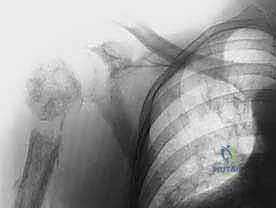

في جراحة استئصال الربع الأمامي التقليدية، يقوم الجراح بإزالة:

1. الطرف العلوي بالكامل: الذراع، الساعد، واليد.

2. لوح الكتف (Scapula): العظمة المثلثة الكبيرة في الظهر.

3. عظم الترقوة (Clavicle): يتم إزالة جزء منها أو إزالتها بالكامل، وهي العظمة التي تربط الكتف بعظم القص.

4. العضلات المحيطة: العضلات التي تربط هذه العظام بالقفص الصدري.

الخطوة 2: الشق الجراحي (Incision)

يستخدم الدكتور هطيف شقاً جراحياً دقيقاً، غالباً ما يكون على شكل مضرب تنس (Racquet-shaped incision). يبدأ الشق من الأمام فوق عظم الترقوة، ويمتد للأسفل نحو الإبط، ثم يلتف للخلف نحو لوح الكتف.